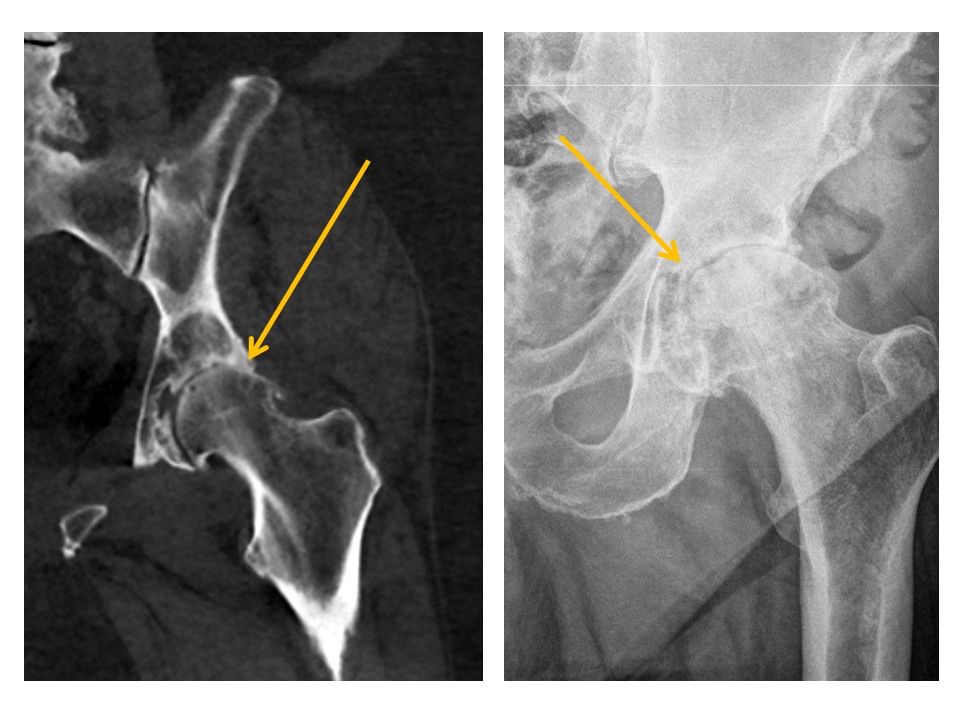

SACRUM and SACROILIAC JOINTS

A fracture is present. [Yes/No]

The sacroiliac joints are widened and asymmetric. [Yes/No]

There is vertical subluxation of the sacroiliac joints. [Yes/No]

INNOMINATE BONES

There are cortical disruptions or displaced fractures. [Yes/No]

Acetabular fractures are present. [Yes/No]